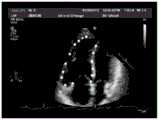

FIG. 5 is a schematic illustration of a position annotation of a cardiac anatomy provided by an embodiment of the present application;

Fig. 4 shows an implementation process of the method for identifying cardiac anatomical structures according to the embodiment of the present application, which includes first acquiring keyframe images of apical four-chamber views of 70 cardiac ultrasound image sequences and position labels of anatomical structures in the images, and a result of the position labeling of the anatomical structures is shown in fig. 5.

As can be seen from comparing fig. 8 and fig. 5, the result of identifying the anatomical structure in the cardiac ultrasound image by using the technical solution of the embodiment of the present application is substantially consistent with the position of the anatomical structure labeled in advance, that is, the technical solution of the embodiment of the present application can accurately identify the anatomical structure in the cardiac ultrasound image.